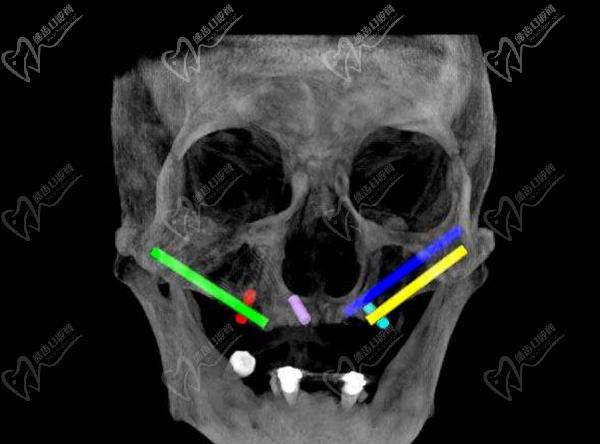

穿顴種植手術(shù),是通過將兩顆超長(zhǎng)植體斜植入顴骨來獲得超高的固位成效,然后在前牙區(qū)在垂直植入2-3顆普通植體,對(duì)于頜骨吸收情況比較重的牙友可以使用四顆穿顴種植體。穩(wěn)定性非常強(qiáng),是即刻種植修復(fù)技術(shù),大大縮短了種植牙時(shí)間,避免了大量植骨帶來的愈合等待期和風(fēng)險(xiǎn)。

在做穿顴種植手術(shù)的時(shí)候,因?yàn)橛袃深w植體斜插入顴骨貫穿面部神經(jīng)和血管區(qū),所以,需要在術(shù)前進(jìn)行詳細(xì)的CBCT頜面檢查,提取上頜竇等影響數(shù)據(jù)來確定非常精密的植入方案,來避免損傷神經(jīng)。大家做穿顴種植手術(shù)的時(shí)候切記要選擇正規(guī)醫(yī)院。

醫(yī)生要詳細(xì)了解術(shù)區(qū)的臨近動(dòng)脈、靜脈、神經(jīng),且植體長(zhǎng)度是常規(guī)植體的3-5倍長(zhǎng),起端極小的角度偏差都會(huì)導(dǎo)致末端的巨大偏離,造成手術(shù)失敗或損傷神經(jīng)的風(fēng)險(xiǎn),手術(shù)精細(xì)度非常高。

穿顴種植手術(shù)一般為上牙列穿顴種植、下牙列all-on-4種植,全口種植流程需要2.5小時(shí)完成,實(shí)現(xiàn)一日得穿顴種植技術(shù)。術(shù)前進(jìn)行全口CT掃描、3D頭骨模擬重建等,精細(xì)確認(rèn)牙友骨量不足的程度、上頜竇底骨質(zhì)薄的數(shù)據(jù),確保手術(shù)更安心。